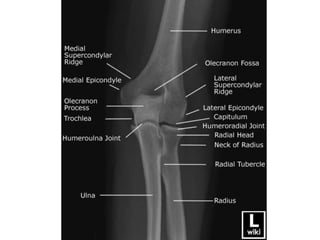

ELBOW

AP & Lateral

• Appearance(Years)

• 1st- Capitulum and lateral

part of trochlea

• 5th – Head of Radius

• 6th- Medial epi. Of

humerus

• 9th- Medial part of

trochlea

• 10th- Top of Olecranon

process

• 12th- Lateral epi. Of

Elbow • Appearance(Years) • 1st-Capitulum and lateral part of trochlea • 5th – Head of Radius • 6th- Medial epi. Of humerus • 9th- Medial part of trochlea • 10th- Top of Olecranon process • 12th- Lateral epi. Of humerus • Fusion • 15th- Olecranon epiphysis with upper end of ulna • 16th – lateral epicondyle, capitulum and trochlea into one mass, and with shaft. • 17th- Head of radius to shaft • 20th – Medial epicondyle of humerus to shaft